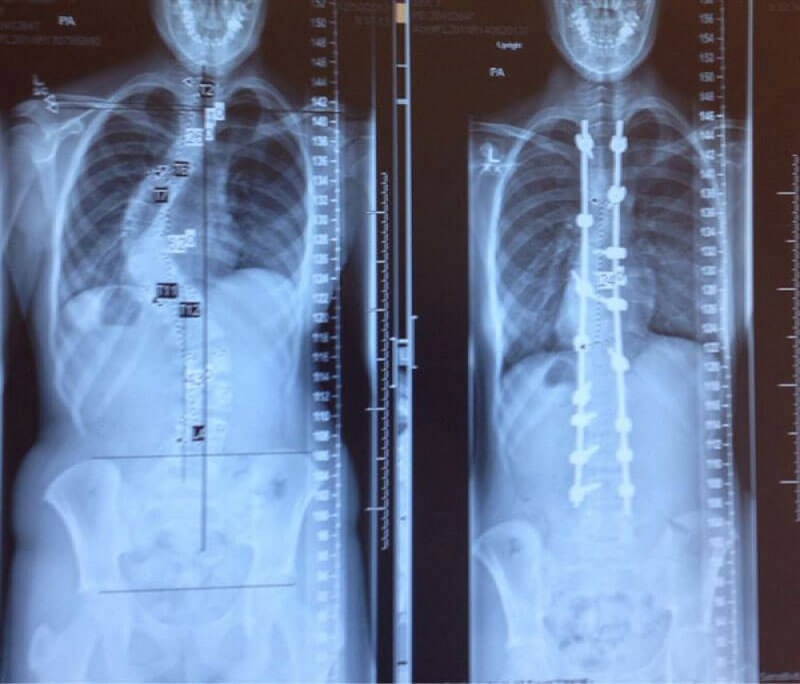

- Radiografías de la columna vertebral, antes y después del tratamiento de la escoliosis.